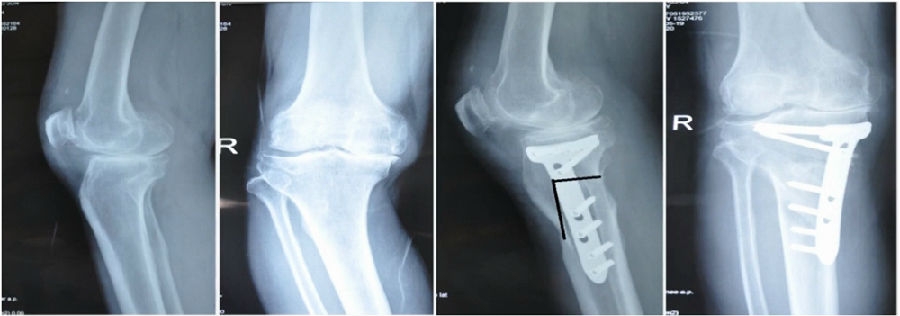

典型病例,男性,57岁,农民,左膝疼痛3年。

术前

术前影像资料

术前规划:

①关节内截骨,内外侧平台平行。

关节内截骨

②再次确定下肢力线。

确定力线

③关节外截骨。

关节外截骨

术中先打克氏针确定截骨方向,先做关节内截骨,截完后测量下肢力线,发现并没达到术前设计的Fujisawa点。

术中影像资料

随后用骨刀继续向前敲,做HTO内侧开放楔,截骨完成后内侧固定,并测量下肢力线,此时达到术前设计的要求。

该患者撑开较大,取了髂骨进行植骨。

术后检查证实达到了术前预期的手术效果,关节线达到了平行,半脱位得到矫正,同时关节线和地面水平。病人行走达到了理想的效果。

术后X线

患者术后4个月截骨愈合,膝关节稳定维持得非常好。

术后4个月